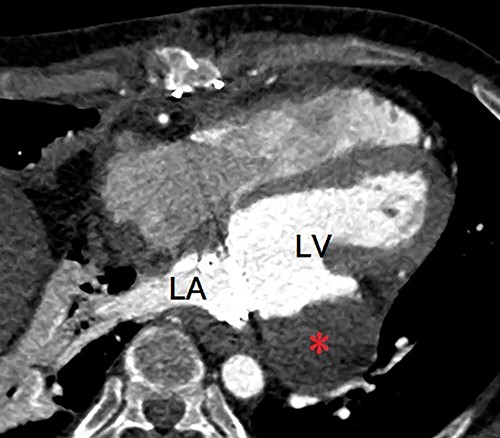

A 40-year-old man was referred to our hospital with suspected LVPA without any symptoms. He had a three-time history of mitral valve surgery, all of which due to infectious endocarditis (IE). Initial mitral valve repair was performed 8 years ago, and MVR were performed 7 years and 4 years ago. In addition, he had a history of severe atopic dermatitis. He had experienced another episode of IE 1 year ago, which was treated with antibiotic therapy. Enhanced computed tomography (eCT) at that time revealed a small nodular contrast region immediately below the mitral valve annulus in the left ventricular muscle. However, the evaluation could not clearly indicate an aneurysm at that point. Transthoracic echography (TTE) at our hospital revealed an LVPA that gradually expanded at the posterior wall immediately below the mitral valve annulus, and the mechanical prosthetic valve had normal function. eCT revealed a massive LVPA that was >50 mm in size (Fig. 1). We decided to close the LVPA due to a risk of future rupture. Thus, the patient underwent his fourth median sternotomy, through which a cardiopulmonary bypass was established with ascending aortic cannulation and bicaval drainage, and the heart was arrested with antegrade cardioplegia. The mitral prosthetic valve was visualized through a right-sided left atriotomy. After removing the valve, the orifice of the aneurysm was confirmed (Fig. 2). Unlike that in the case of active IE, the tissue around the aneurysm was not vulnerable; thus, the orifice was closed using a bovine pericardial patch (Fig. 3A). In addition, BioGlue (CryoLife Inc., Kennesaw, GA, USA) was injected into the aneurysm (Fig. 3B). The aneurysm was filled with BioGlue to prevent blood flowing into it. Thereafter, MVR was performed using a 25-mm On-X heart valve (CryoLife Inc., Kennesaw, GA, USA). Postoperative eCT revealed complete closure of the aneurysm (Fig. 4). The patient’s cardiac function was good, and no paravalvular leakage was observed on TTE. He was discharged home without complications. At the 10-month follow-up, the size of the aneurysm found to be reduced, as revealed using TTE.

Postoperative enhanced computed tomography showing absent flow into the pseudoaneurysm (asterisk). LA, left atrium; LV, left ventricle.